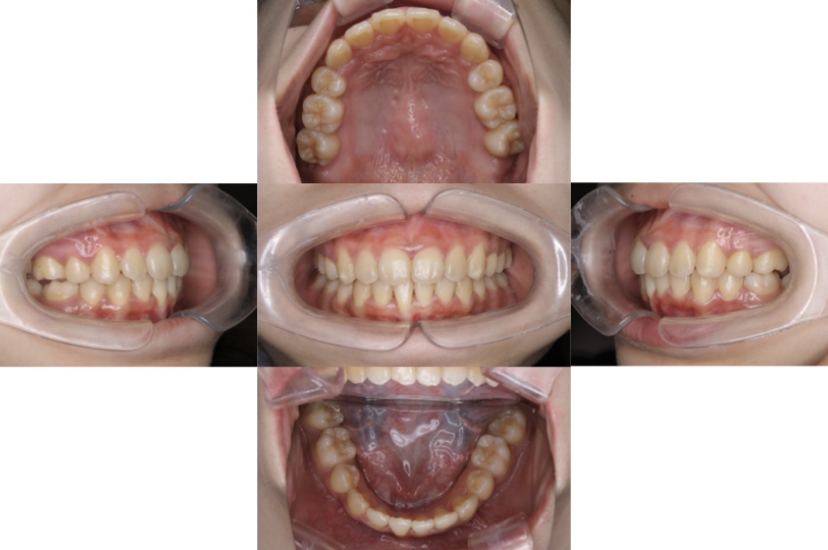

症例3

叢生

抜歯

ブラケット矯正

上下顎叢生(上下の前歯のガタガタ)のケースです。

装置はラビアル(上下表側)で、上下顎の小臼歯を4本抜歯を行っています。抜歯したスペースを使って、上下の前歯の後方移動と叢生(ガタガタ)の改善を行っています。

主訴 八重歯を治したい。

年齢・性別 25歳 女性

お住まいの地域 神奈川県川崎市

治療方針 抜歯スペースを利用して上前歯の叢生(ガタガタ)の改善

抜歯部位 上下顎左右第一小臼歯

使用装置 ラビアル(上下表側)、顎間ゴム

治療期間 1年11か月

治療回数 16回

リテーナー クリアリテーナー

BEFORE

AFTER